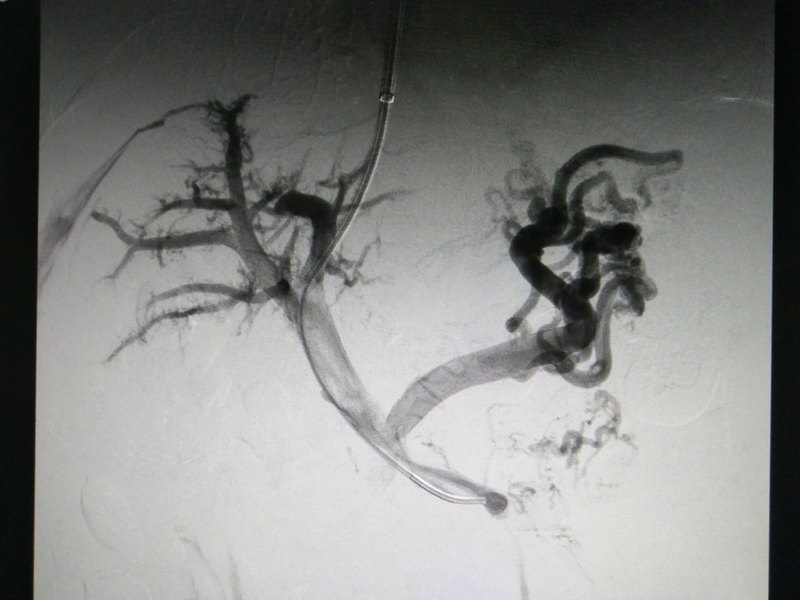

腦梗塞既人們常說的“中風(fēng)”的主要原因是腦供血?jiǎng)用}的狹窄和閉塞。據(jù)統(tǒng)計(jì),60%以上的腦缺血病人是由頸動(dòng)脈狹窄引起。 頸動(dòng)脈是人腦的主要供血?jiǎng)用}之一,當(dāng)出現(xiàn)不同程度的狹窄時(shí),大腦也就出現(xiàn)不同程度的缺血。主要的表現(xiàn)為:耳鳴、視物模糊、頭痛、頭暈、記憶力減退、乏力、嗜睡、失眠以及多夢(mèng)等。也可以出現(xiàn)眩暈、眼前發(fā)黑(黑矒),重者可以出現(xiàn)反復(fù)的暈厥,甚至偏癱、失語、昏迷,少數(shù)人可以有視力下降,偏盲、復(fù)視,甚至突發(fā)性失明。 頸動(dòng)脈狹窄的治療方式有三種:藥物治療、頸動(dòng)脈內(nèi)膜剝脫術(shù)和頸動(dòng)脈支架植入術(shù)。 藥物治療是長(zhǎng)期服用抗血小板藥(如常規(guī)服用阿司匹林、或新的強(qiáng)效抗血小板藥物氯吡格雷),但僅適用于狹窄程度不超過50%的患者,對(duì)于超過70%狹窄的患者一般建議手術(shù)治療。 頸動(dòng)脈開刀手術(shù)的基本方法是內(nèi)膜切除,解除動(dòng)脈狹窄和粥樣硬化斑塊,恢復(fù)大腦血供,消除腦梗塞栓子,該手術(shù)的缺點(diǎn)是需要全身麻醉,頸部切口及創(chuàng)傷大,恢復(fù)慢,優(yōu)點(diǎn)是完全切除增生內(nèi)膜和硬化斑塊,再發(fā)生狹窄的機(jī)會(huì)較小,不需要終身服用抗血小板及抗凝藥物。 頸動(dòng)脈支架植入術(shù)具有創(chuàng)傷小、操作簡(jiǎn)單、起效快、恢復(fù)快、療效確切、可重復(fù)操作的優(yōu)點(diǎn)。只需要局部麻醉,在大腿根部穿刺,將一根直徑在2毫米左右的導(dǎo)管放置入股動(dòng)脈,將導(dǎo)管輸送到頸動(dòng)脈狹窄部位,選準(zhǔn)位置后將支架釋放出來就完成了對(duì)頸動(dòng)脈硬化狹窄部位的擴(kuò)張成型,改善大腦血流供應(yīng)。 當(dāng)出現(xiàn)以下情況時(shí)需進(jìn)行手術(shù)或腔內(nèi)治療:1、頸動(dòng)脈狹窄程度超過70%;2、頸動(dòng)脈狹窄程度小于70%,但頭暈、黑矒等腦缺血癥狀典型,或者硬化斑塊不穩(wěn)定,容易脫落;3、藥物治療效果不佳,有中風(fēng)發(fā)作史,或腦梗塞后仍有小中風(fēng)發(fā)作。 病例介紹如下: 女性,69歲,主主因間斷性黑懵,頭暈入院,無四肢肌力、肌張力障礙,既往無糖尿病病史,高血壓病史多年口服降壓藥物控制平穩(wěn),當(dāng)?shù)蒯t(yī)院彩超提示雙側(cè)頸內(nèi)動(dòng)脈重度狹窄就診我院,頭頸部CTA顯示右側(cè)頸內(nèi)動(dòng)脈長(zhǎng)段閉塞,左側(cè)頸內(nèi)動(dòng)脈起始端極重度狹窄,右側(cè)椎動(dòng)脈起始端重度狹窄。治療策略先行右側(cè)椎動(dòng)脈支架植入,目的防止因頸動(dòng)脈支架植入過程中血壓波動(dòng)造成后循環(huán)梗塞可能,而后再行左側(cè)頸動(dòng)脈支架植入,過程如下圖所示: 頸動(dòng)脈狹窄行支架植入術(shù)的效果鼓舞人心,患者的接受程度也很高,國(guó)際上很多對(duì)比內(nèi)膜切除術(shù)和支架成型術(shù)試驗(yàn)的結(jié)果表明,頸動(dòng)脈支架成型術(shù)較內(nèi)膜切除術(shù)安全、創(chuàng)傷小、恢復(fù)快。 對(duì)于接受頸動(dòng)脈支架植入的患者而言,金屬支架是異物,在體內(nèi)與血液接觸時(shí)有血小板聚集和形成血栓的可能,因此術(shù)后需正規(guī)口服抗凝、抗血小板藥物。通常用藥為阿司匹林100mg,1次/日,口服終身,波立維(氯吡格雷)75mg,1次/日,口服3-6個(gè)月。術(shù)后1,3,6,9,12個(gè)月時(shí)復(fù)查頸動(dòng)脈超聲或CT,以后每年復(fù)查一次。術(shù)后維持良好的生活習(xí)慣:嚴(yán)格戒煙、清淡低鹽低脂飲食;積極活動(dòng)鍛煉身體;積極控制好血壓、血糖及血脂水平。